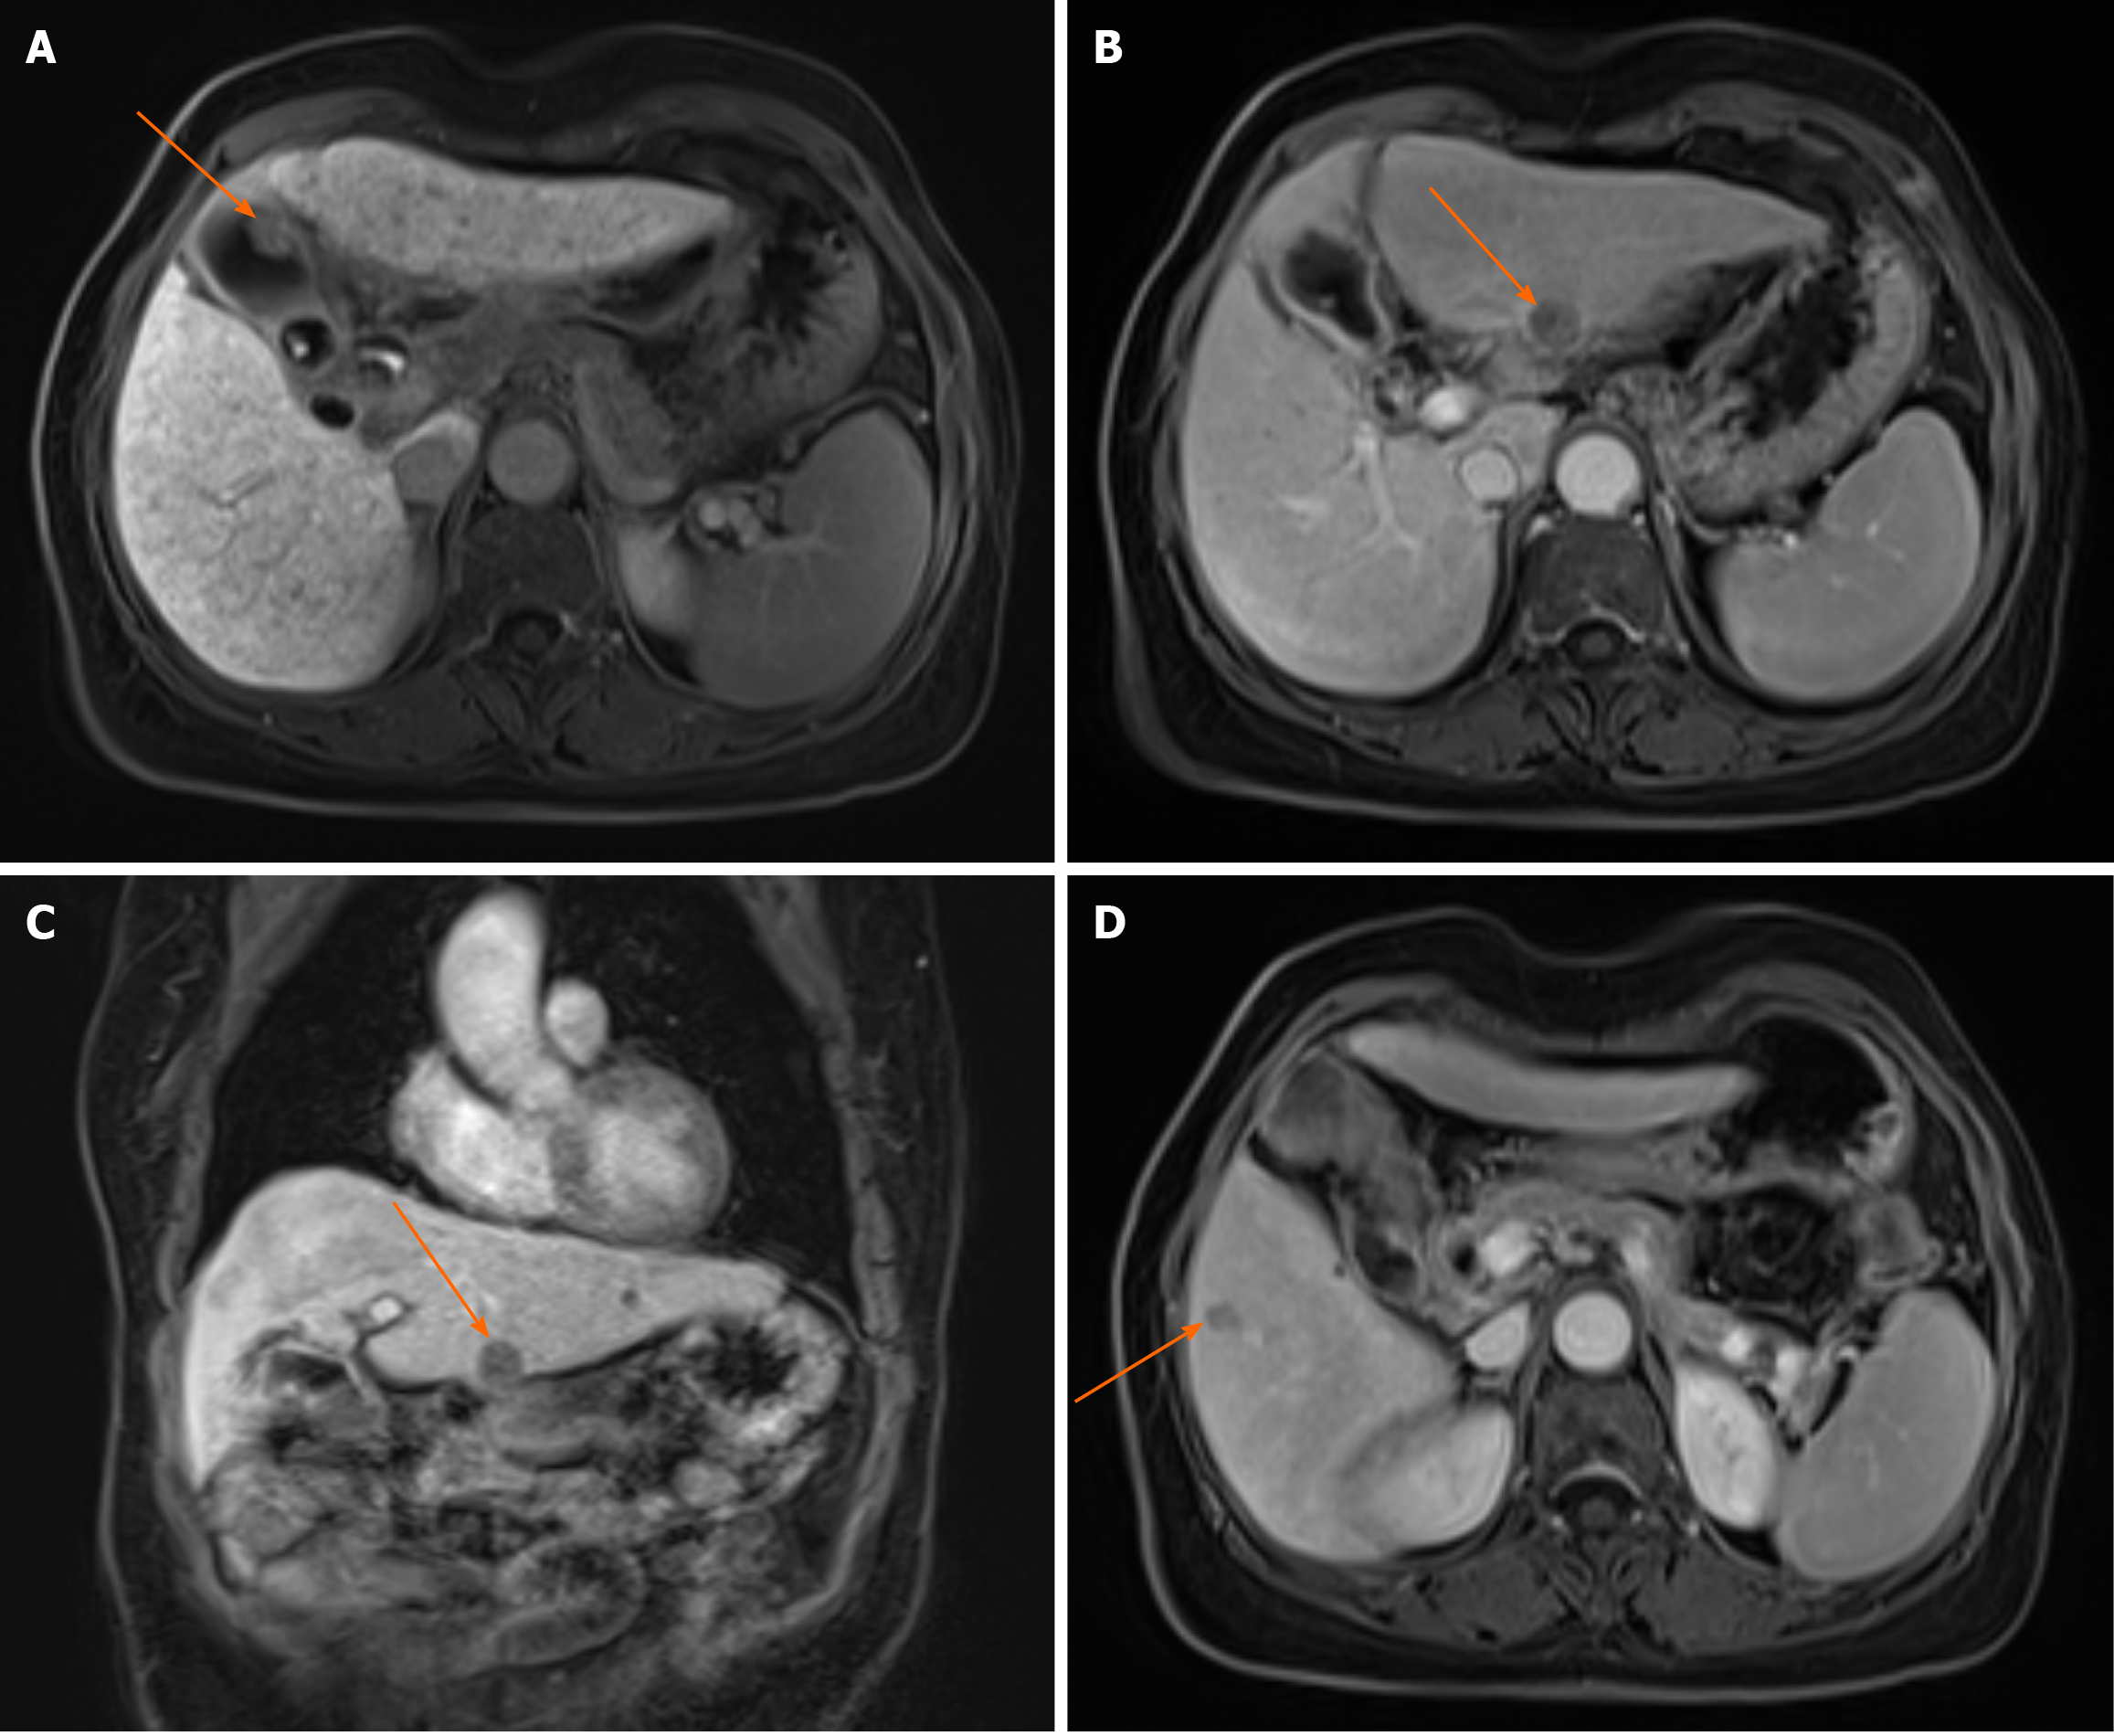

Figure 2 Abdominal magnetic resonance imaging scan.

A: Abdominal magnetic resonance imaging (MRI) scan showing a 2.0 cm × 1.0 cm mass in the gallbladder. Arrow: Gallbladder mass (axial view); B: Abdominal MRI scan showing a 1.6 cm × 1.5 cm lesion in the left lateral lobe of the liver. Arrow: Liver lesion (axial view); C: Abdominal MRI showing a 1.6 cm × 1.5 cm lesion in the left lateral lobe of the liver. Arrow: Liver lesion (coronal view); D: Abdominal MRI scan showing a 1.0 cm × 0.8 cm lesion in segment VI of the liver. Arrow: Liver lesion (axial view).